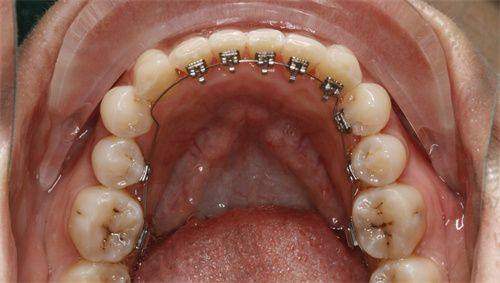

正畸安氏分类是由Angle医生提出的,主要根据磨牙的咬合关系来进行分类。第一类,即中性错合,上下颌第一磨牙的咬合关系正常,但是可能存在牙列拥挤、牙间隙等其他问题。第二类是远中错合,上颌第一磨牙的近中颊尖咬合在下颌第一磨牙的近中颊沟的远中。第三类是近中错合,上颌第一磨牙的近中颊尖咬合在下颌第一磨牙的近中颊沟的近中。通过这样的标准,医生可以初步判断患者牙齿错合的类型。

诊断正畸安氏分类需要专精的医生进行全方面的检查。首先,医生会进行口腔的视诊,观察牙齿的排列、咬合情况等。然后,可能会借助X光片,如全景片、头颅侧位片等,来了解牙齿和颌骨的具体情况。此外,还会取牙齿模型,进行详细的测量和分析。通过这些综合的检查手段,医生能够正确地判断患者属于正畸安氏分类中的哪一类,为后续的治疗提供依据。

安氏一类错合虽然磨牙关系正常,但牙列的不整齐也会影响美观和口腔健康。比如牙列拥挤可能导致清洁困难,容易引发龋齿和牙周疾病。安氏二类错合常表现为上颌前突或下颌后缩,会影响面部的美观,使侧面看起来不够协调。安氏三类错合则可能出现下颌前突,俗称“地包天”,不仅影响外观,还可能影响咀嚼功能。

对于安氏一类错合,如果是牙列拥挤,可能会采用拔牙或扩弓的方式来排齐牙齿。对于安氏二类错合,早期可以使用功能矫治器促进下颌的生长,后期配合固定矫治器进行精细调整。对于安氏三类错合,轻度的可以通过正畸治疗进行掩饰性矫治,重度的则可能需要正畸和正颌联合治疗。具体的方案需要医生根据患者的具体情况来制定。